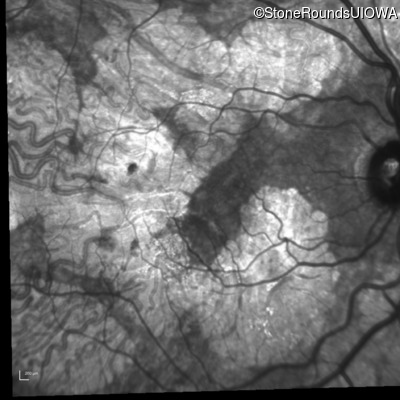

Age at visit: 51 years

OD OS

This 51 year old woman first experienced some abnormality in her distance vision when she was 27 years old. She feels that her vision has been stable since that time.